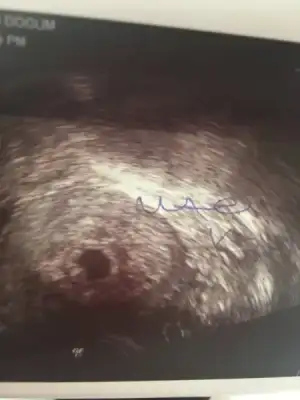

Beklemek çok zor gerçekten inş herşey güzel olacakGunaydin hanimlar bende inşallah haziran annesi olacağım ama cok korkuyorum 5+3 te gittim kese 5mm. 15 gun sonra gel gec dollenmedir dedi ama toxoplazma yüzünde bir düşük yaşadım cok korkuyorum çok da dua ediyorum.

İnsallah hepimiz sağlıkla alırız kucagimiza bebeklerimizi. Su bir hafta gecmeyecek bana![]()